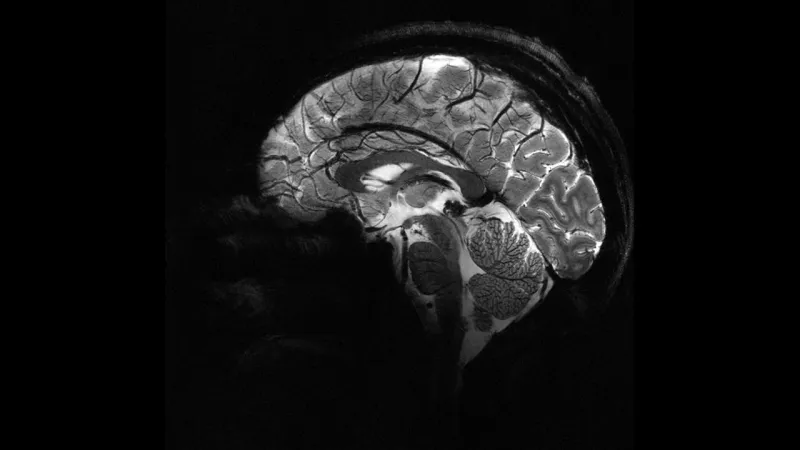

Avustralyalı bilim insanları, epilepsi hastası çocukların hayatını değiştirecek bir yapay zeka aracı geliştirdi. Bu çığır açan teknoloji, doktorların gözden kaçırabildiği küçük beyin malformasyonlarını tespit ederek, çocukların daha hızlı ve etkili tedaviye erişmesine olanak tanıyor. Uzmanlar, bu sistemin hayat kurtarıcı operasyonlara erişimi kolaylaştıracağını vurguluyor.

Epilepsi, dünya genelinde milyonlarca insanı etkileyen nörolojik bir rahatsızlık. Özellikle çocuklarda görülen epilepsi vakalarında, erken ve doğru teşhis büyük önem taşıyor. Ancak bazı durumlarda, beyindeki küçük lezyonlar geleneksel yöntemlerle tespit edilemeyebiliyor. İşte bu noktada yapay zeka devreye girerek, gizli kalmış hasarları ortaya çıkarıyor. Bu sayede, çocukların daha doğru bir şekilde teşhis edilerek uygun tedavi yöntemlerine yönlendirilmesi sağlanıyor.